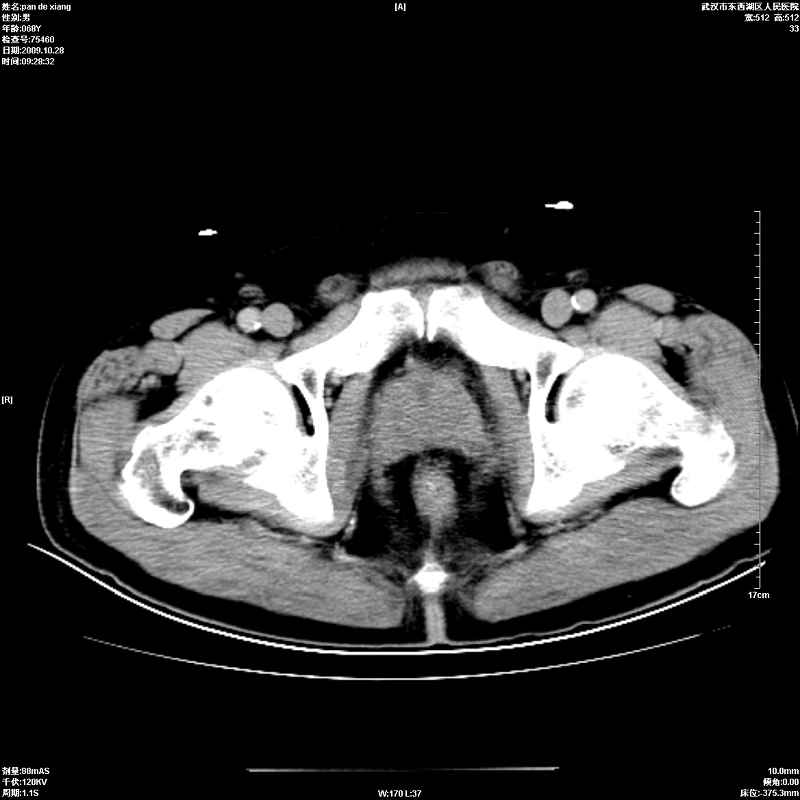

以下是引用杀毒软件在2009-10-28 20:41:00的发言:[br]结合临床考虑---白血病双肾改变或淋巴瘤。

以下是引用zxl51642在2009-10-29 9:59:00的发言:[br]结合临床“单克隆免疫球蛋白血症”,考虑双肾为继发损害并肾功能不全(尿中大量igg及少量iga、igm等大分子免疫球蛋白滤出所致继发损害),椎前软组织肿块为髓外造血。与浆细胞瘤有区别,平扫时有战友说的很清楚。